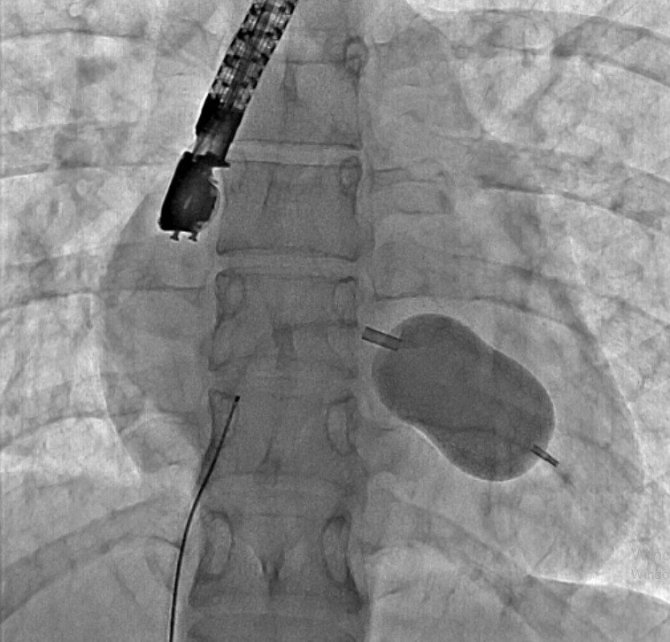

Eskişehir Şehir Hastanesi'nde ilk defa mitral balon operasyonu yapıldı. Operasyon, anjiyografi cihazı ile adım adım kaydedildi.

Eskişehir Şehir Hastanesi'nde Kardiyoloji Uzmanı Dr. Mehmet Özgeyik ve 4 kişilik ekibi tarafından ilk defa mitral balon operasyonu yapıldı. Türkiye'de az sayıda yapılan kalp kapağı balon işlemiyle yeni anne olmuş genç bir hasta sağlığına kavuştu. Bu sayede hastalar ameliyat olmaktan, ömür boyu kan sulandırıcı ilaçlar kullanmaktan ve metal bir kalp kapağı ile yaşamaktan kurtuluyor.

Gerçekleşen başarılı operasyon hakkında konuşan Kardiyoloji Uzmanı Dr. Mehmet Özgeyik, "Bu işlemi genellikle kalp kapaklarında ciddi darlık olan genç hastaların kişilere uyguluyoruz. Buradaki amacımız ameliyat olmadan, kasıktan küçük iki damar yolu açarak hastalarımızın kapak darlıklarını uzun süreli olarak genişletmeyi hedefliyoruz. Burada 23 yaşında yeni anne olmuş genç bir hastamıza müdahale yaptık. Hastamız ya kapak ameliyatı olacaktı ya da bu işlem sayesinde kapak darlığını aşmayı planlıyorduk. İşlem gayet başarılı oldu. Hastamızın kapak darlığını genişlettik. En azından 10-15 sene boyunca ameliyata gerek kalmadan hastamızı ilaç tedavisiyle takip etmeyi planlıyoruz" diye konuştu.

Cerrahi operasyonlar yerine mitral balon işlemiyle hastaları sağlıklarına kavuşturmak istediklerini aktaran Dr. Özgeyik, "Hastanemizde ilk kez yapılan bir işlem. Bu işlem için uygun hasta bulmak biraz zor oluyor çünkü çok sık yapılan bir işlem değil. Fakat gelecekte hasta portföyümüzün de artması ile birlikte daha sık yapmayı planlıyoruz. En azından hastalarımızı büyük bir cerrahi operasyona vermeden böyle küçük işlemlerle hayat kalitelerini artırmayı planlıyoruz. Hastamız ameliyata gitmiş olsaydı büyük bir operasyon geçirmiş olacaktı. Göğüs bölgesinde büyük bir kesiğe maruz kalacaktı. Aynı zamanda ömür boyu kullanması gereken farklı ilaçlar olacaktı. Hasta kendisine ait olmayan metal bir kapakla yaşamak zorunda kalacaktı. Biz bu işlemde hastaya kasıktan iki tane damar yolu açtık. Hastaya neşter ile kesme işlemi uygulamaktan kurtardık. Ayrıca hastanın hayatı boyunca kullanacağı kan sulandırıcı ilaçları uzunca bir süre ertelemiş olduk. En önemlisi de hastanın kendi kalp kapağını kullanmasını sağlamış olduk ve metal kapak yükünden kurtulmuş oldu" şeklinde konuştu.